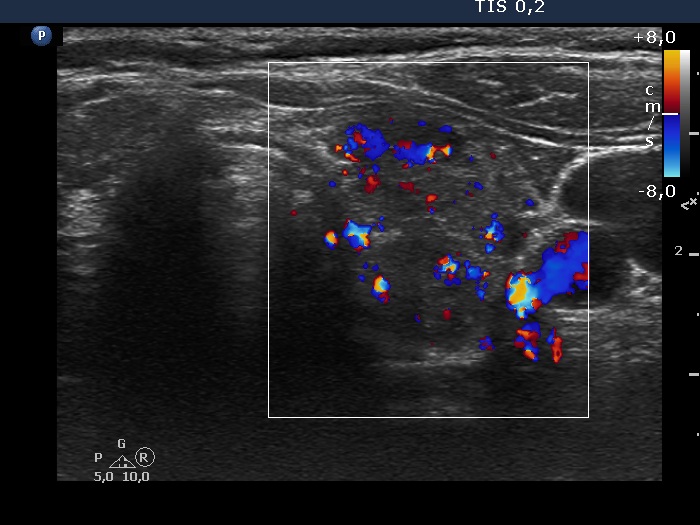

Left lobe, transverse scan, color Doppler mode. The vascularization is not specific.